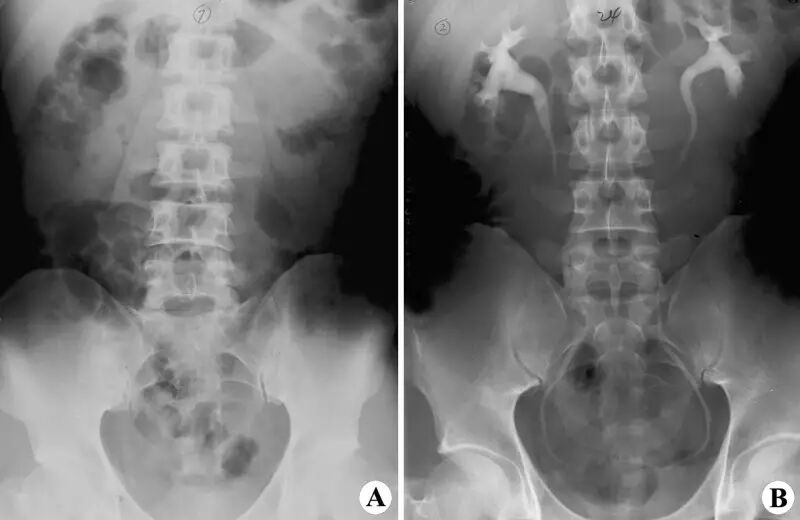

9. 泌尿系及男性生殖系造影:检查前1天的晚餐应吃软食,此后就要禁食。检查前1天的晚上还要服泻药以清除肠腔内的积气、积粪。检查之前要排空小便。